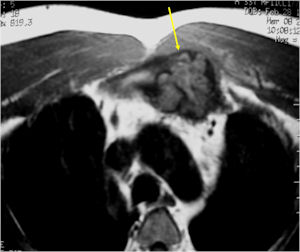

MRI:

- Also useful in determining extent

- There is often extensive edema around the tumor in the surrounding bone and soft tissues that can lead to a misdiagnosis of a malignant tumor.

- Most have a similar radiographic appearance as a conventional osteoblastoma and have well defined margins, variable amounts of mineralization and peritumoral sclerosis. They occasionally have radiographic characteristics consistent with malignancy.